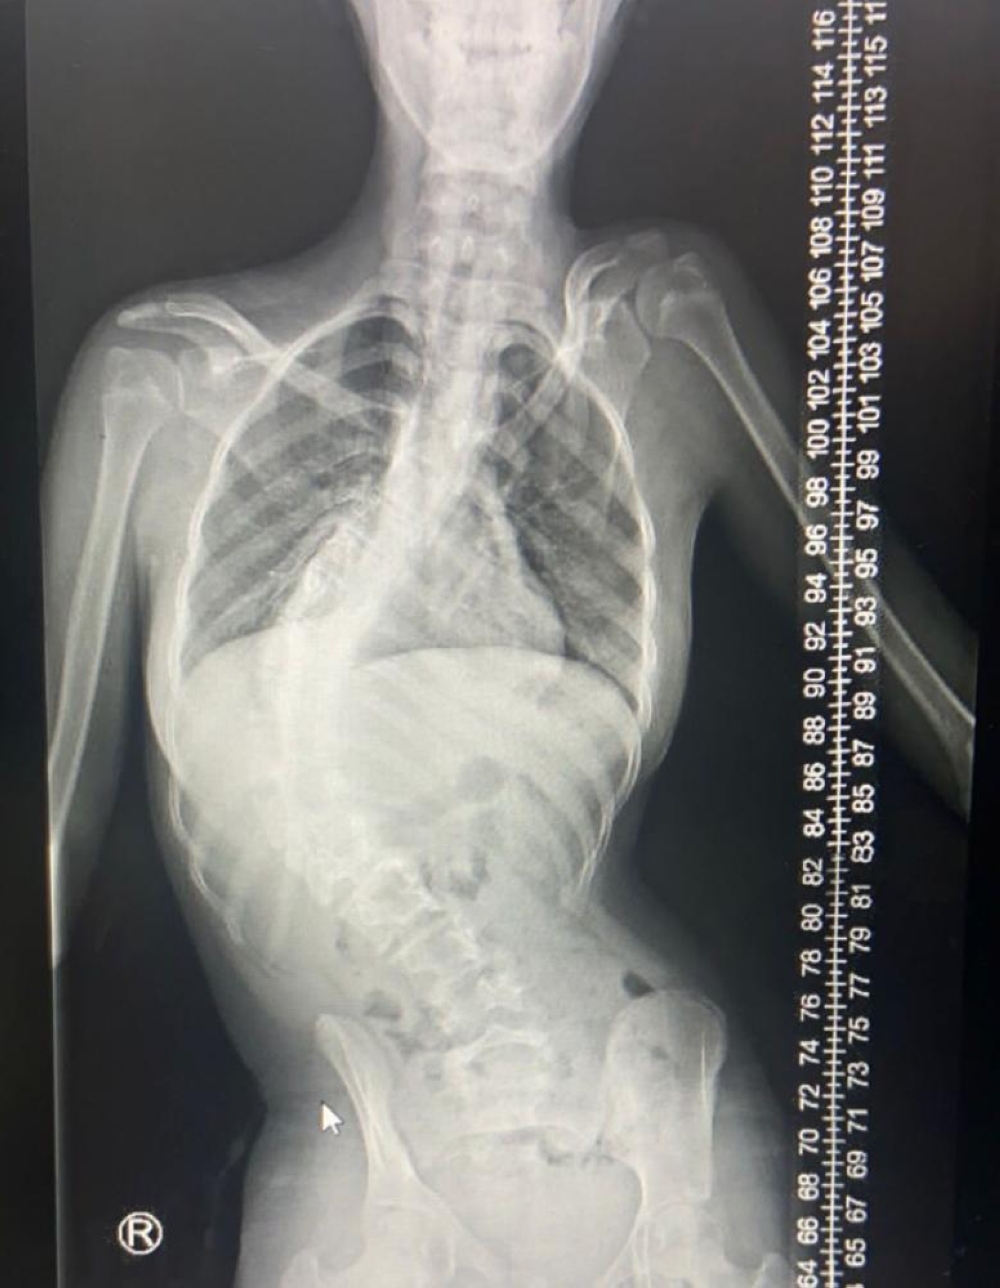

وأوضحت إخصائي تأهيل إصابات العمود الفقري الدكتورة ماجدة العتيبي، أن الجنف هو انحراف جانبي للعمود الفقري غالبًا ما يُشخَّص خلال فترة المراهقة، مشيرة إلى أن بعض المصابين بحالات مثل الشلل الدماغي والخلل العضلي عرضة للإصابة به، كما أن الأسباب وراء غالبية حالات الجَنف التي تصيب الأطفال غير معروفة وقد تكون جينية.

وأضافت أن أغلب الحالات تكون بسيطة ولكن في بعضها تزداد الانحناءات سوءا مع نمو الطفل، وربما تتسبب هذه الانحناءات الشديدة في الإصابة بإعاقات أخرى غير التشوه الداخلي الذي تكون بدايته بدون أعراض تذكر، مشيرة إلى أن الحالة تزداد سوءاً عندما يقلص انحناء العمود الفقري الشديد من مقدار المساحة الموجودة داخل الصدر، مما يجعل من الصعب على الرئتين العمل بطريقة صحيحة، ويترتب عليها صعوبة التنفس والحاجة للتدخل الجراحي كأمر طارئ للحفاظ على حياة المصاب.

التفاف العمود الفقري أو دورانه بالإضافة إلى تقوسه من جانب إلى آخر